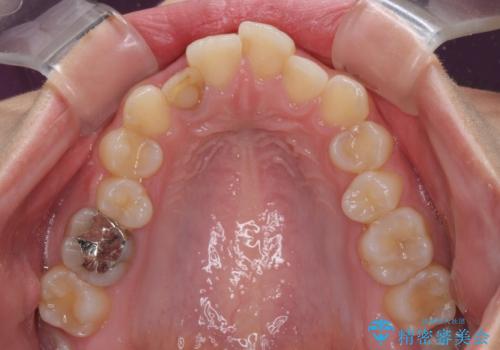

- 前歯の歯並びと不自然な色をした前歯のクラウンを気にして来院された患者様です。

上下前歯の歯列不正はインビザラインにより歯列を整え、その後に、前歯をオーダーメイドタイプのオールセラミッククラウンにて補綴治療することとしました。

前歯のデコボコを一番気にしていらっしゃいましたが、矯正治療により下顎前歯が隠れるほどのディープバイトも一緒に改善され、奥歯に負担のかかりにくい咬み合わせとなりました。